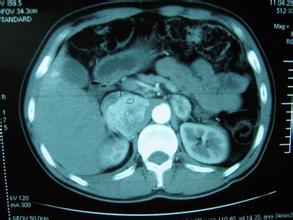

近日,一则关于体检发现有肚子有足球大小肿瘤的新闻被各大新闻媒体所转载。新闻中的当事人今年26岁,毕业后一直没有找到满意的工作。一个月前面试一家满意的工作后,按公司要求去做体检。谁知道体检B超显示,其右腹部一个22*23cm的巨大肿瘤,像个足球一样占据了大半个腹腔,且还挤压肝脏和肾脏导致肝脏肾脏挪了位。

经医生进一步检查,发现其是肾上腺嗜铬细胞瘤。由于此病比较罕见,且手术有一定的风险性,医生历时三个小时,才将这个足球大小的肿瘤切除。期间,由于手术过程中患者出现血压波动,最高甚至达到250/119毫米汞柱,因此手术中暂停过三次。